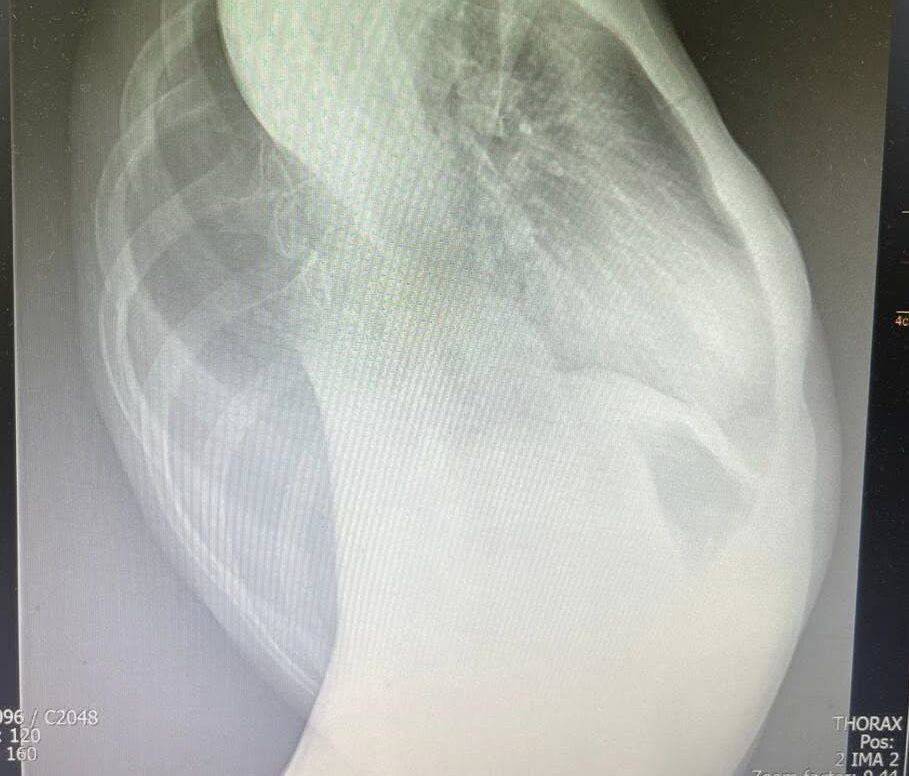

Переломним етапом стало рішення провести комп’ютерну томографію (КТ), яка і виявила справжню причину проблем: у дівчинки — глибока деформація грудної клітки зі сколіозом. Через значне викривлення хребта одна з легенів була здавлена настільки, що почалися незворотні зміни у легеневій тканині — хронічний фіброз.

Складність випадку вимагала командної та мультидисциплінарної роботи. У цьому випадку оперативне втручання — єдиний спосіб зупинити прогресування деформації, зняти тиск з легені та покращити якість життя дитини.

До слова, глибока деформація грудної клітки зі сколіозом — це складне викривлення хребта, при якому порушується не лише його осьова лінія, а й форма та симетрія ребер і грудної клітки. У таких випадках ребра можуть з одного боку виступати, а з іншого — западати, що спричиняє зміщення внутрішніх органів, ускладнення дихання та порушення серцево-судинної діяльності.